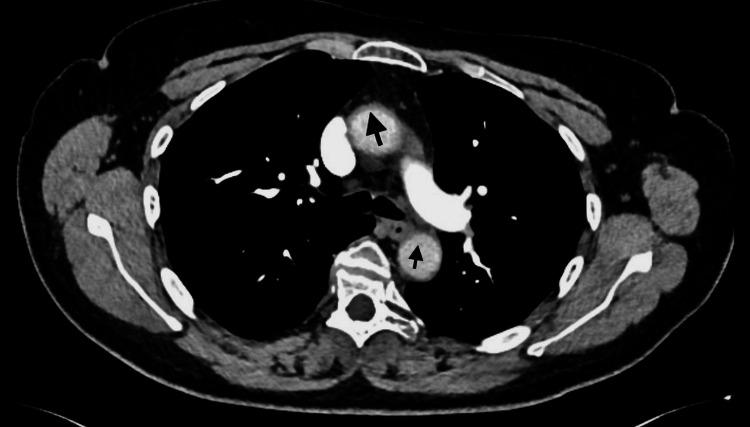

Giant-cell arteritis (GCA) is a type of vasculitis characterised by the presence of granulomas. It is the predominant form of systemic vasculitis in adults and primarily affects the larger arteries in individuals aged ≥ 50 years. GCA affects the major arteries, such as the aorta and its branches, particularly the outer branches of the external carotid artery. Signs and symptoms can be categorised into cranial, extracranial, and systemic manifestations. Patients with headaches, jaw claudication, and vision disturbances usually have extracranial branches of the external carotid artery. Aside from being the prevailing manifestation of GCA, our primary concern regarding this variant is the potential for irreversible vision loss if not properly identified and addressed. Conversely, the GCA can also affect other major blood vessels such as the aorta. Here, we present the case of a 70-year-old Caucasian female patient with cranial GCA who had experienced a temporal headache three years prior. The patient was successfully treated with prednisolone, which was gradually reduced to a very low level with the assistance of methotrexate. Recently, the patient presented with a dry cough that lasted for two months and elevated inflammatory markers. After thorough research, it was determined that there was no evidence of infection, including atypical infections, and that no abnormalities were found in the lungs. Ultimately, via an 18F-fluorodeoxyglucose-positron emission tomography (FDG-PET) scan, the patient was diagnosed with large vessel giant cell arteritis (LV-GCA). This impacted the aorta, carotid arteries, and subclavian arteries. The patient experienced notable improvement in her cough and a reduction in inflammatory markers after receiving a high dosage of oral prednisolone. This case exemplifies the unusual manifestation of LV-GCA and verifies that recurring symptoms may differ from the original presentation. While dry cough is not commonly listed as a symptom of LV-GCA, it can be present as a manifestation or the sole presentation in certain patients, particularly when inflammatory markers are consistently high and there is no pulmonary disease.

巨细胞动脉炎(GCA)是一种以肉芽肿存在为特征的血管炎。它是成人系统性血管炎的主要形式,主要影响年龄≥50岁个体的较大动脉。GCA影响主要动脉,如主动脉及其分支,特别是颈外动脉的外周分支。体征和症状可分为颅内、颅外和全身表现。有头痛、颌部间歇性运动障碍和视力障碍的患者通常累及颈外动脉的颅外分支。除了是GCA的主要表现外,我们对这种变体的主要担忧是,如果未得到正确识别和处理,可能会导致不可逆的视力丧失。相反,GCA也可影响其他主要血管,如主动脉。在此,我们报告一例70岁白种女性颅部GCA患者,该患者三年前曾出现颞部头痛。患者接受泼尼松龙治疗成功,在甲氨蝶呤的辅助下逐渐减至非常低的剂量。最近,该患者出现持续两个月的干咳且炎症标志物升高。经过全面检查,确定没有感染证据,包括非典型感染,肺部也未发现异常。最终,通过18F-氟脱氧葡萄糖正电子发射断层扫描(FDG-PET),该患者被诊断为大血管巨细胞动脉炎(LV-GCA)。病变累及主动脉、颈动脉和锁骨下动脉。该患者在接受高剂量口服泼尼松龙后,咳嗽明显改善,炎症标志物降低。本病例例证了LV-GCA的不寻常表现,并证实复发症状可能与最初表现不同。虽然干咳通常未被列为LV-GCA的症状,但在某些患者中可能作为一种表现或唯一表现出现,特别是当炎症标志物持续升高且无肺部疾病时。